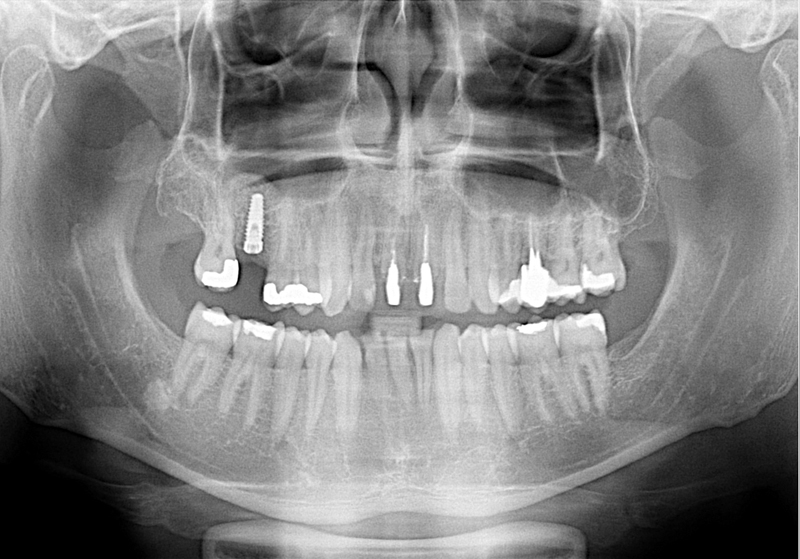

Sinus lift

Nejčastější oblastí pro doplnění kosti je čeleni dutina horní čelisti.

Tento výkon se nazývá sinus lift - aplikace kostního granulátu do čelistní dutiny

Při ztrátě molárů a premolárů v horní čelisti a jejich náhradě implantáty se často setkáváme s nedostatečnou vertikální nabídkou kosti pod čelistní dutinou, často doprovázenou i nedostatečnou horizontální nabídkou a sníženou kvalitou kosti

(v oblasti 2. premoláru v 50%, v oblasti moláru až v 80% případů nedostatečná kostní nabídka)

Od roku 1985 je tento problém řešen augmentační operací nazývanou sinus lift.

Jedná se o vyzvednutí membrány, která čelistní dutinu vystýlá, pod vyzvednutou membránou vznikne kapsa, kam se umístí augmentační materiál, do kterého se zavedou implantáty.

Vhojení implantátů se při této operaci prodlužuje na 6-12 měsíců.